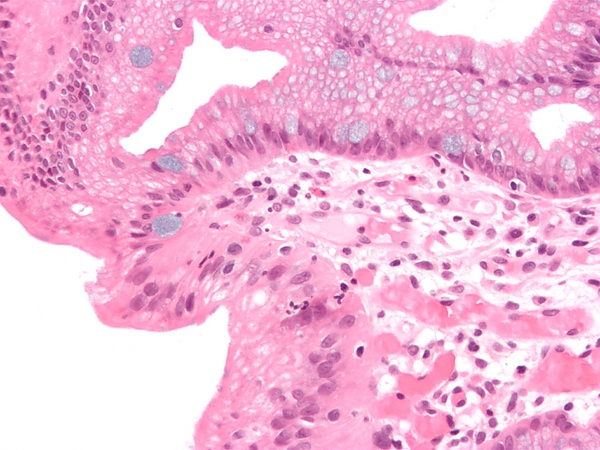

При появлении физиологических или патологических стрессовых факторов, клетки могут реагировать несколькими способами. Одним из вариантов адаптации является метаплазия — доброкачественное изменение тканевой структуры в ответ на хроническое физическое или химическое раздражение. Например, курение вызывает замещение мерцательного эпителия дыхательных путей многослойным плоским эпителием. Плоскоклеточная метаплазия может развиваться в мочевом пузыре (причина — цистит, конкременты мочевого пузыря), в шейке матки (причина — гормональная стимуляция, изменение pH влагалищной среды, инфекции) и т. д.[1]